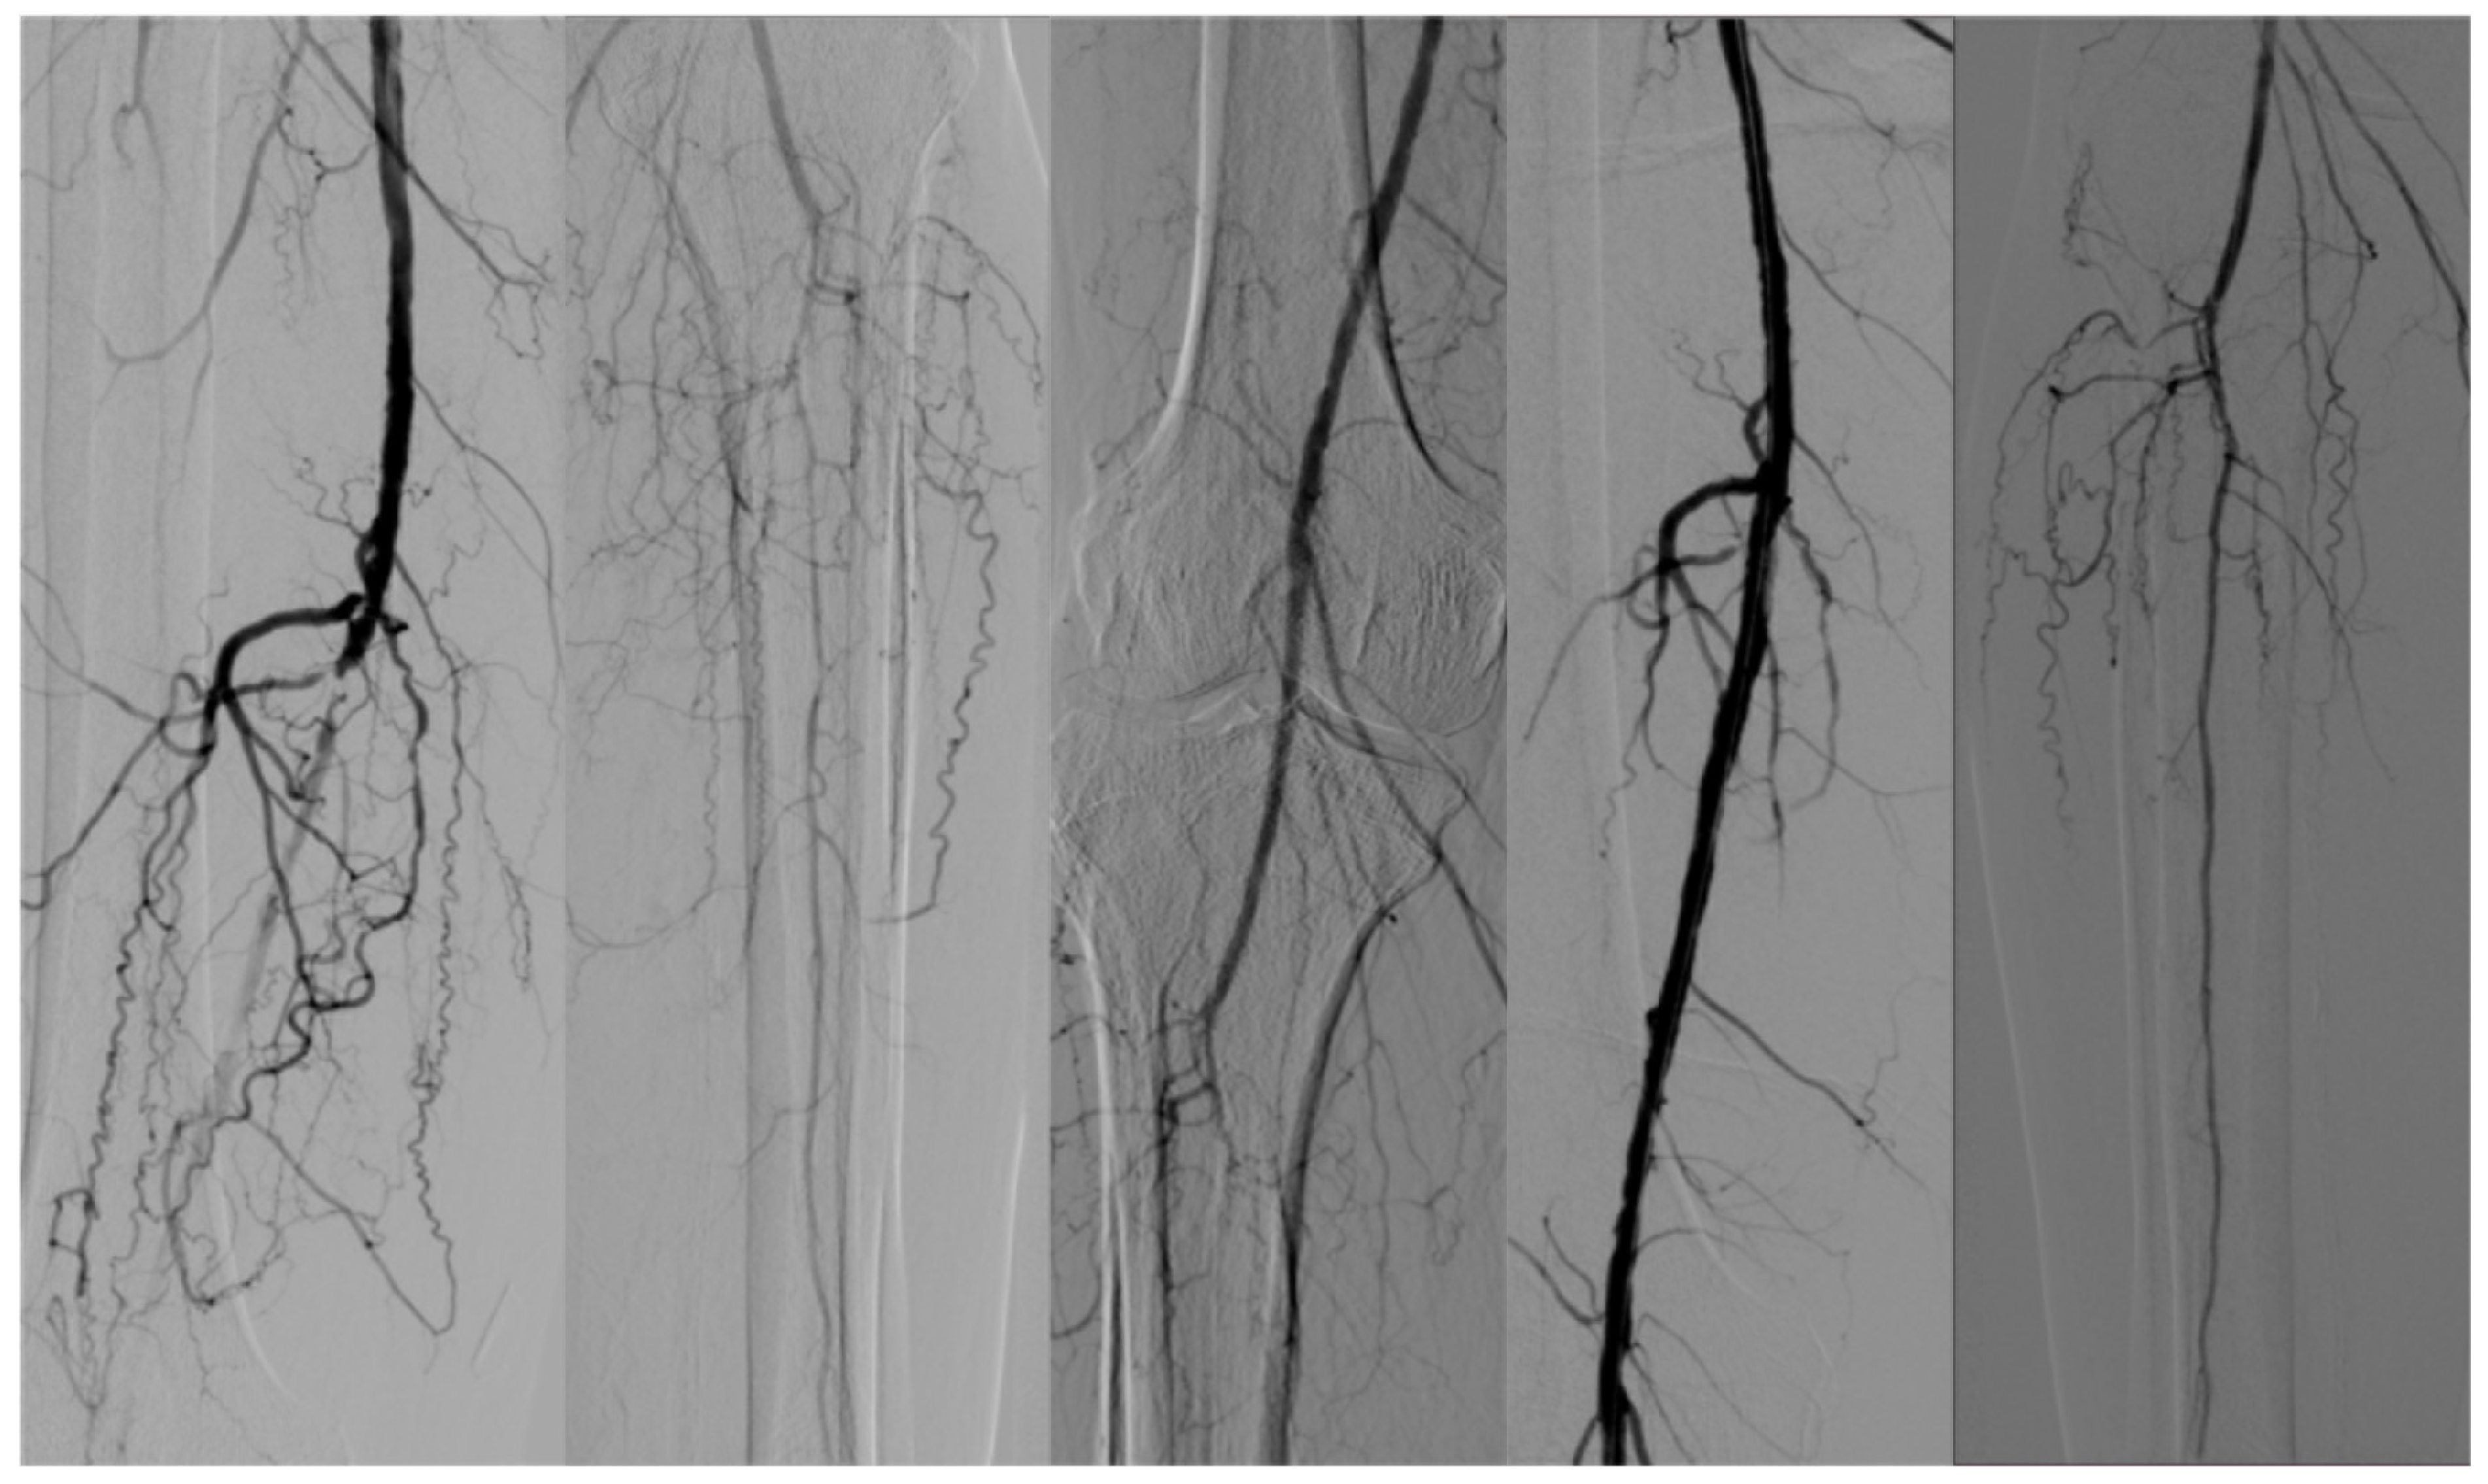

1. Introduction

2. Materials and Methods